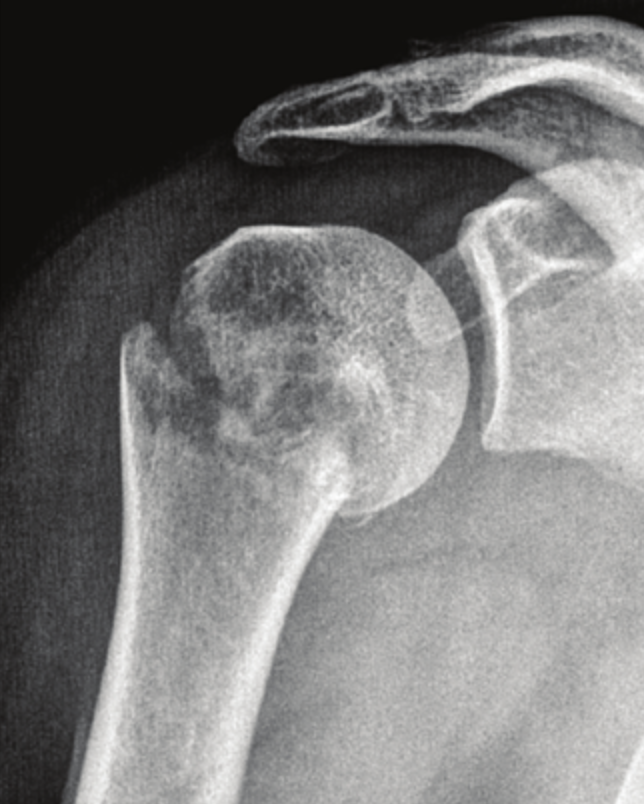

X-ray image of a shoulder joint with a fractured humerus.

A proximal humerus fracture is a break that occurs near the top of the upper arm bone, close to the shoulder joint.